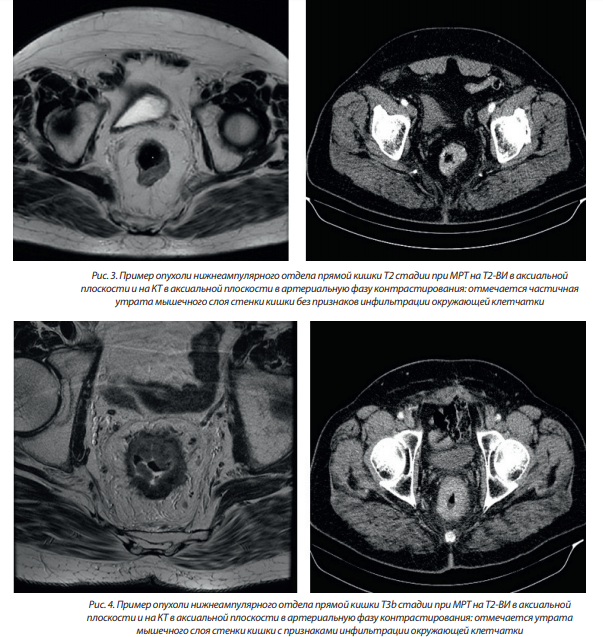

– Т2 — опухоль прорастает подслизистый слой и распространяется в мышечную оболочку;

– ТЗ — опухоль прорастает мышечную оболочку и выходит за пределы стенки прямой кишки в мезоректальную клетчатку (в забрюшинных отделах) или субсерозную оболочку (в перитонизированной части);

Примеры опухолей различной Т стадии приведены на рис. 3–5.